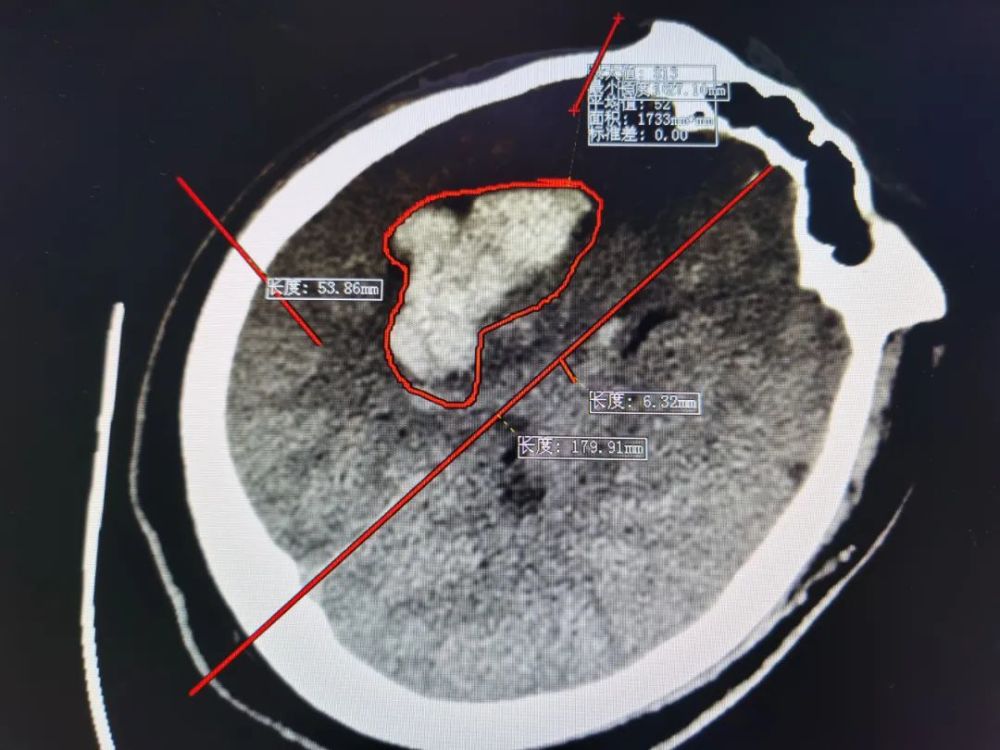

虽然我对病人的CT结果已经有所准备,但真的看见这结果是却又替他担心起来。

多巴胺曾经不止一次说过,一个病人如果符合以下四点中的三点便要考虑脑出血:意识障碍+头痛+呕吐+血压升高。

而眼前这位26岁的年轻患者呢?

他的头颅CT检查结果如下,红色圈中的白色区域便是出血。

看见这个结果时,患者的父母尚且不能接受:“才26岁就脑出血了?”